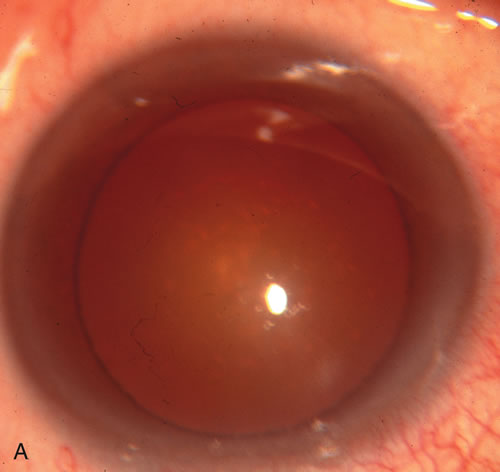

Fig. 3. Partial bleb failure following clear corneal phacoemulsification with foldable IOL. A. Preoperative bleb appearance prior to temporal lens extraction. Preoperative IOP was 12 mm Hg on no antiglaucoma medications. Time from 5-FU trabeculectomy surgery to lens extraction was one year. B. Bleb appearance 2 months after clear corneal cataract surgery with topical anesthesia. Following lens extraction, increased vascularity was noted along with decreased size of the filtering bleb. IOP increased to 20 mm Hg as early as 2 weeks after surgery, necessitating topical antiglaucoma therapy. C. High magnification view of bleb before lens extraction demonstrates diffuse pale bleb. D. High magnification view of bleb 2 months after surgery. There are vessels surrounding the nasal side of the bleb and the overall bleb size is smaller.